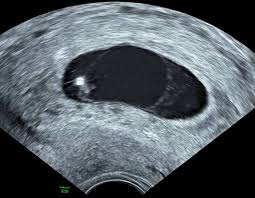

Der Dottersack Ein Wichtiger Marker Beim Ultraschall In Der Fruhschwangerschaft Springerlink